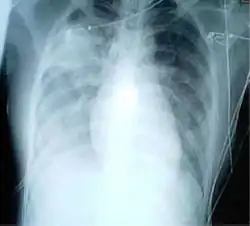

Das Röntgenbild der Lunge eines SARS-Patienten zeigt diffuse fleckförmige Verdichtungen oder sogenanntes „Milchglas“ über beiden Unterfeldern, welche die Lappengrenzen überschreiten. Im Vergleich zu einer typischen bakteriellen Lungenentzündung findet sich kein positives Bronchopneumogramm.